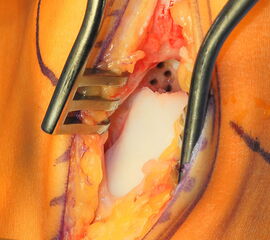

Operationstechnik (Fotos und Video)

Je nach Lage des Knorpeldefektes sind verschiedene Zugänge möglich. Ziel ist einen guten Zugang zum Defekt zu erreichen bei gleichzeitiger Vermeidung einer Innenknöchelosteotomie.

Die Darstellung der weiteren Operationstechnik erfolgt am Beispiel eines medialen Zugangs bei einer Osteochondrosis dissceans mit subchondraler Zyte der medialen Talusschulter (siehe MRT Abbildung 1).